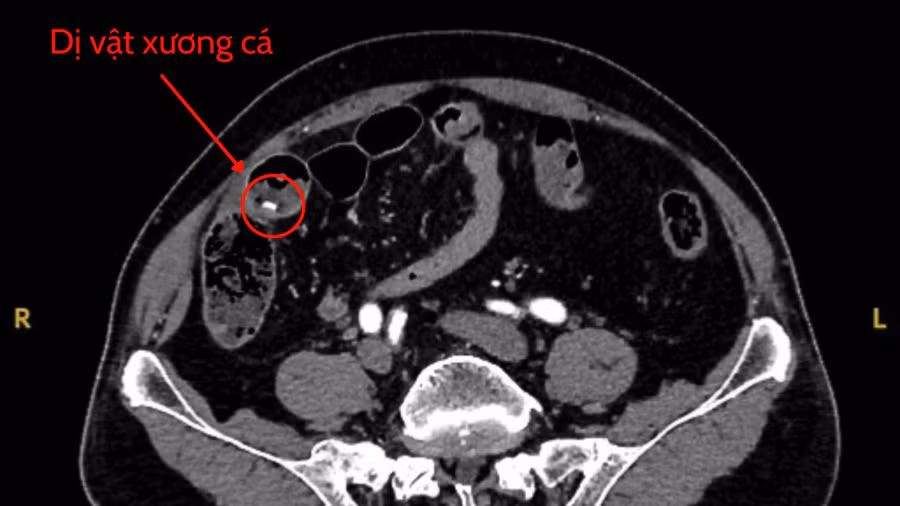

Kết quả chẩn đoán hình ảnh ghi nhận một dị vật cản quang dài khoảng 4cm xuyên thủng thành ruột non, gây viêm phúc mạc toàn thể, một tình trạng nhiễm trùng nguy hiểm.

BS.CKII Nguyễn Vũ An - Trưởng khoa Ngoại tổng quát nhận định đây là ca bệnh nguy cấp, ekip khoa tiến hành phẫu thuật khẩn cấp. Trong quá trình mổ, các bác sĩ phát hiện một mẩu xương cá đâm thủng ruột non.